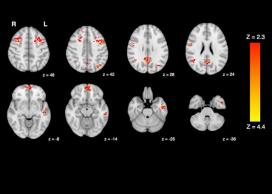

Traffic pollution impairs brain function

A new study by UBC and University of Victoria researchers has shown that common levels of traffic pollution can impair human brain function in only a matter of hours. The findings show that just two hours of exposure to diesel exhaust causes a decrease in the brain’s functional connectivity – a measure of how different areas of the brain interact and communicate with each other. The study provides the first evidence in humans, from a controlled experiment, of altered brain network connectivity induced by air pollution.